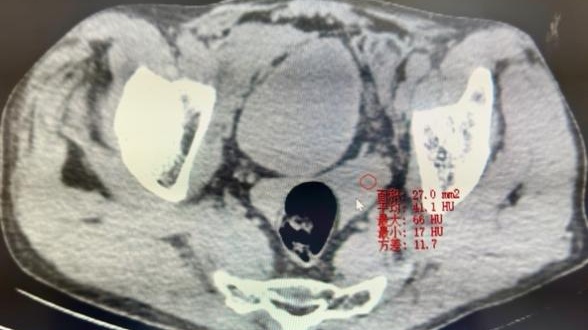

虽然是在医技科室开展援助工作,但作为医疗“侦察兵”的汤医生深知每一次精准的影像诊断都是对患者生命的尊重和守护。有一位患者因车祸伤来放射科进行胸腹部CT平扫检查,CT诊断为创伤性膈疝及肋骨骨折,但汤医生凭借其丰富的经验和敏锐的观察力,发现患者的肝脏外缘处有少许略高密度影及盆腔内血性积液,提示极大可能存在腹腔内脏损伤,该患者手术证实为局部肝破裂。汤医生的精准洞察不仅为患者及时解除病痛,更避免了潜在的严重并发症,充分展现了放射科医生在医疗团队中的重要角色,也为当地医生树立了榜样。